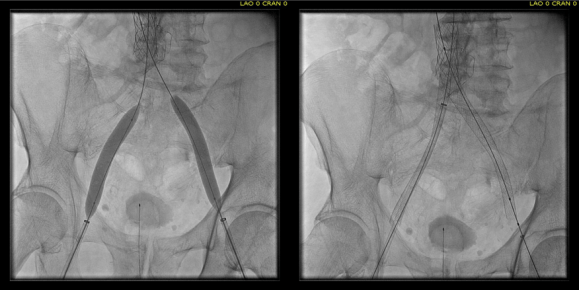

Examination revealed a fit and trim man in his 70’s in no apparent distress. He had bilateral leg edema that was moderate with small superficial and tender ulcers of the right posterior distal calf. Pulses were normal. He was taken to our hybrid suite and venography from femoral vein access in the proximal thigh in the supine position revealed his right and left iliac venous systems to be occluded (below figures).

right initial venogram

Right injection from femoral sheath showing occluded iliac vein with collaterals

left initial venogram.png

Left injection